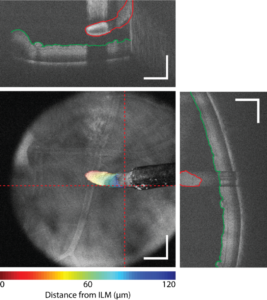

Low vision and blindness affect over 40 million Americans and have an estimated annual cost of $25 billion for clinical diagnosis and treatment. The prevalence of visual impairment in adults 40 years and older in the United States is above 3.5% and expected to increase markedly due to population aging. Many ocular diseases are progressive and require surgical management at advanced stages, which involves precision manipulation of delicate semi-transparent structures in the eye. Optical coherence tomography (OCT) has revolutionized ophthalmic imaging by allowing for high-resolution noninvasive visualization of retinal microstructure and has become the “gold standard” for clinical diagnostics. However, despite broad adoption of preoperative OCT for surgical planning and predicting outcomes, postoperative functional outcomes may be highly variable. In macular hole (MH) surgery, ~90% of patients achieve hole closure and anatomic normalization but as low as 27% of patients achieve a best-corrected visual acuity of >20/40 (legal driving limit). We hypothesize that (1) structural changes in the retina during MH repair, which are prognostic of postoperative visual function, result directly from surgical intervention; (2) iOCT imaging of MH dynamics during surgery will enable quantification of image-based biomarkers and identification of corresponding tissue-instrument interactions that lead to poor functional outcomes; and (3) understanding the causal relationship between surgical manipulation and postoperative vision will benefit clinical decision-making and novel surgical technique and intraoperative feedback mechanism development for MH repair and other ocular diseases. Our collaborative program of engineers and clinicians will perform foundational imaging studies to understand the casual effects that surgical maneuvers have on postoperative vision recovery during MH repair. To overcome limitations of current-generation iOCT systems, we have developed multimodal spectrally encoded coherence tomography and reflectometry (SECTR) technologies that allows for simultaneous and intrinsically co-registered en face reflectance and cross-sectional OCT imaging. SECTR uses concurrently acquired spectrally encoded reflectance (SER) en face and OCT cross- sectional images to provide complementary spatial information in orthogonal dimensions and enable volumetric registration and tracking. Segmentation of motion-corrected 4D OCT datasets in post-processing has enabled retinal layer identification and quantification of tissue deformations resulting from surgical manipulation. Automated tracking and 4D imaging of MH dynamics (AIM 1) provides unprecedent data on structural changes resulting from surgical manipulation that have been shown to be predictive of postoperative functional outcomes (AIM 2). In vivo iSECTR imaging during MH repair will be performed to understand the causal relationship between surgical dynamics and postoperative visual function (AIM 3) and may lead to novel image-guided surgical maneuvers. Technologies developed during this project will have broad applications in personalized surgery, predicting outcomes, and image-guided feedback in a wide-range of surgical specialties.